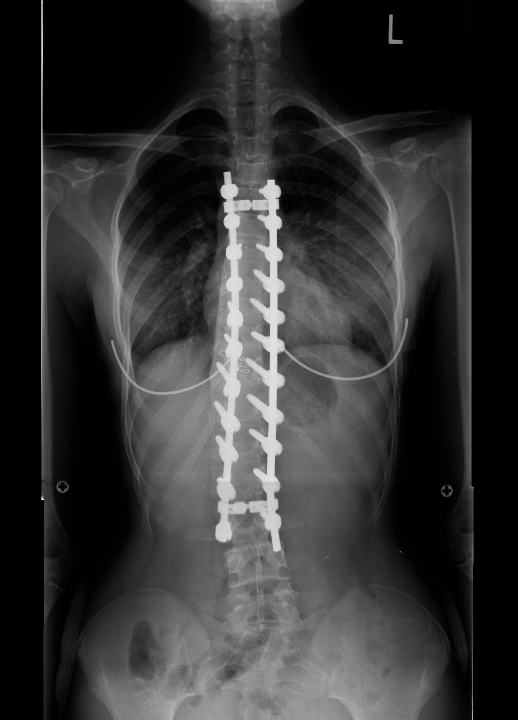

| Pre-op | Post-op |